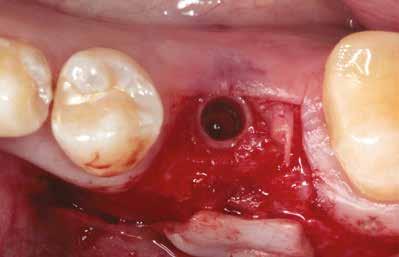

A részleges extrakció befejezése után következhet az implantátumágy preparálása a gyártó utasításai szerint (6.

kép). A bemutatott esetben Nobel Replace CC 4,3x13mm implantátumot helyeztünk be, amely a bukkális oldalon direkt kontaktusba került a megmaradt foggyökérdarabbal (7. kép). Az alveolus oldalfalai és a körszimmetrikius implantátum közötti hézag kitöltésére bovin eredetű xenograftot (Creos S xenogain) használtunk (8. kép). A hasonló

6. kép: Implantátum-ágy preparáció. 7. a–b. képek: Implantátum behelyezés. 8. kép: A behelyezett implantátum. 10. a–b képek: Azonnali ideiglenes korona készítése. 9. kép: Megfelelő primer stabilitás.